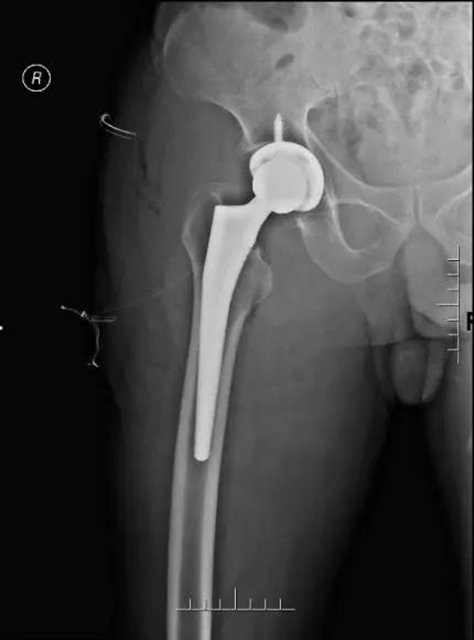

2022年5月4日,五一节假期的最后一天,经由神经内科、心血管内科、心身医学科、康复医学科会诊评估后,在骨与关节外科 、麻醉科、手术室的通力合作下,由李忠教授、尹一然副教授、鲜海医师共同为张婆婆实施了全麻下右髋关节半髋置换术。术后张婆婆安全返回病房,第二天便开始下地活动。

张婆婆术后X线